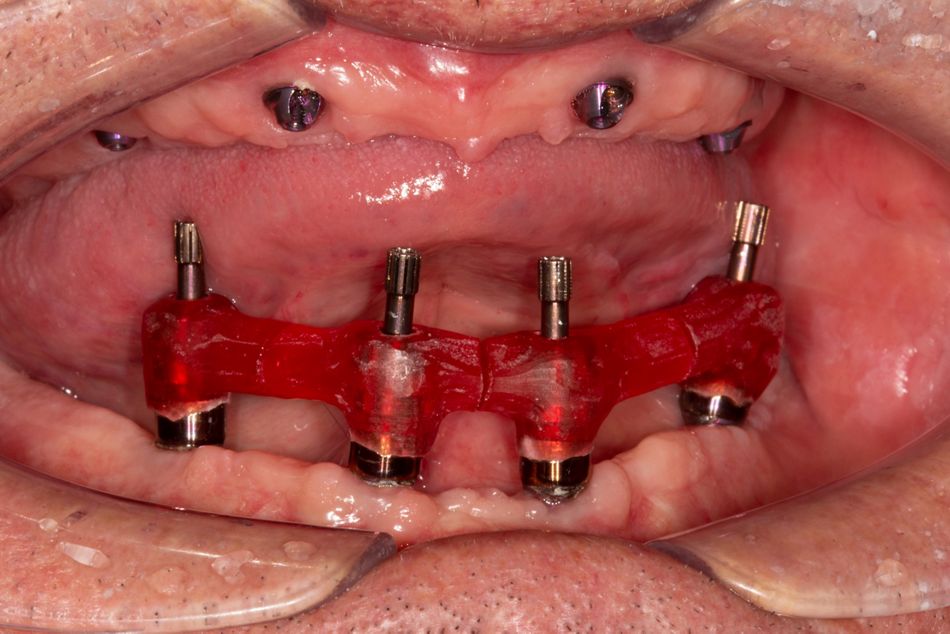

Das Eindrehmoment lag zwischen 40 und 60Ncm. Die Implantate wurden mit Screw-retained-Abutments (SRA`s) versorgt (O°, 30°) (Abb. 10). Im Anschluss an den Wundverschluss erfolgten Abdrucknahme (Impregum® 3M Espe, Löffel: Miratray®) (Abb. 11) und Bissregistrierung (individuelle Bisschablone, Occufast®, Zhermak). Zuletzt wurden die Zähne 33 und 43 entfernt. Das aus Kaltpolimerisat hergestellte mit Glasfaser verstärkte Langzeitprovisorium (Abb. 12) wurde nach ca. 3 Stunden eingegliedert (Abb. 13 OPG Post OP UK). Zum Zeitpunkt der Nahtentfernung nach einer Woche zeigte sich eine weit fortgeschrittene Heilung.

Der Patient tolerierte den ersten Eingriff sehr gut, so dass ca. 5 Wochen nach der Implantation im Unterkiefer die Versorgung des Oberkiefers vorgenommen werden konnte. Im gleichen Modus (Antibiose, Lokalanästhesie, i.v.-Sedierung) beließ man, wie bereits im Unterkiefer, zunächst die Zähne 13 und 23 zur Orientierung bei der Bisslagebestimmung. In den Regionen 15, 12, 22 und 25 wurden BLX®-Implantate des Durchmesser 4,5mm eingebracht sowie mit SRA´s (30°, 17°) versorgt (Abb. 14 -17).

Es wurde eine erneute Abdrucknahme mit Verblockung der Abdruckpfosten vorgenommen (Pattern Resin®, GC). Nach einer Ästhetikeinprobe erfolgte die finale Versorgung mit einem individuell mit PMMA verblendeten gefrästen Gerüst (Abb. 22, 23, 24).